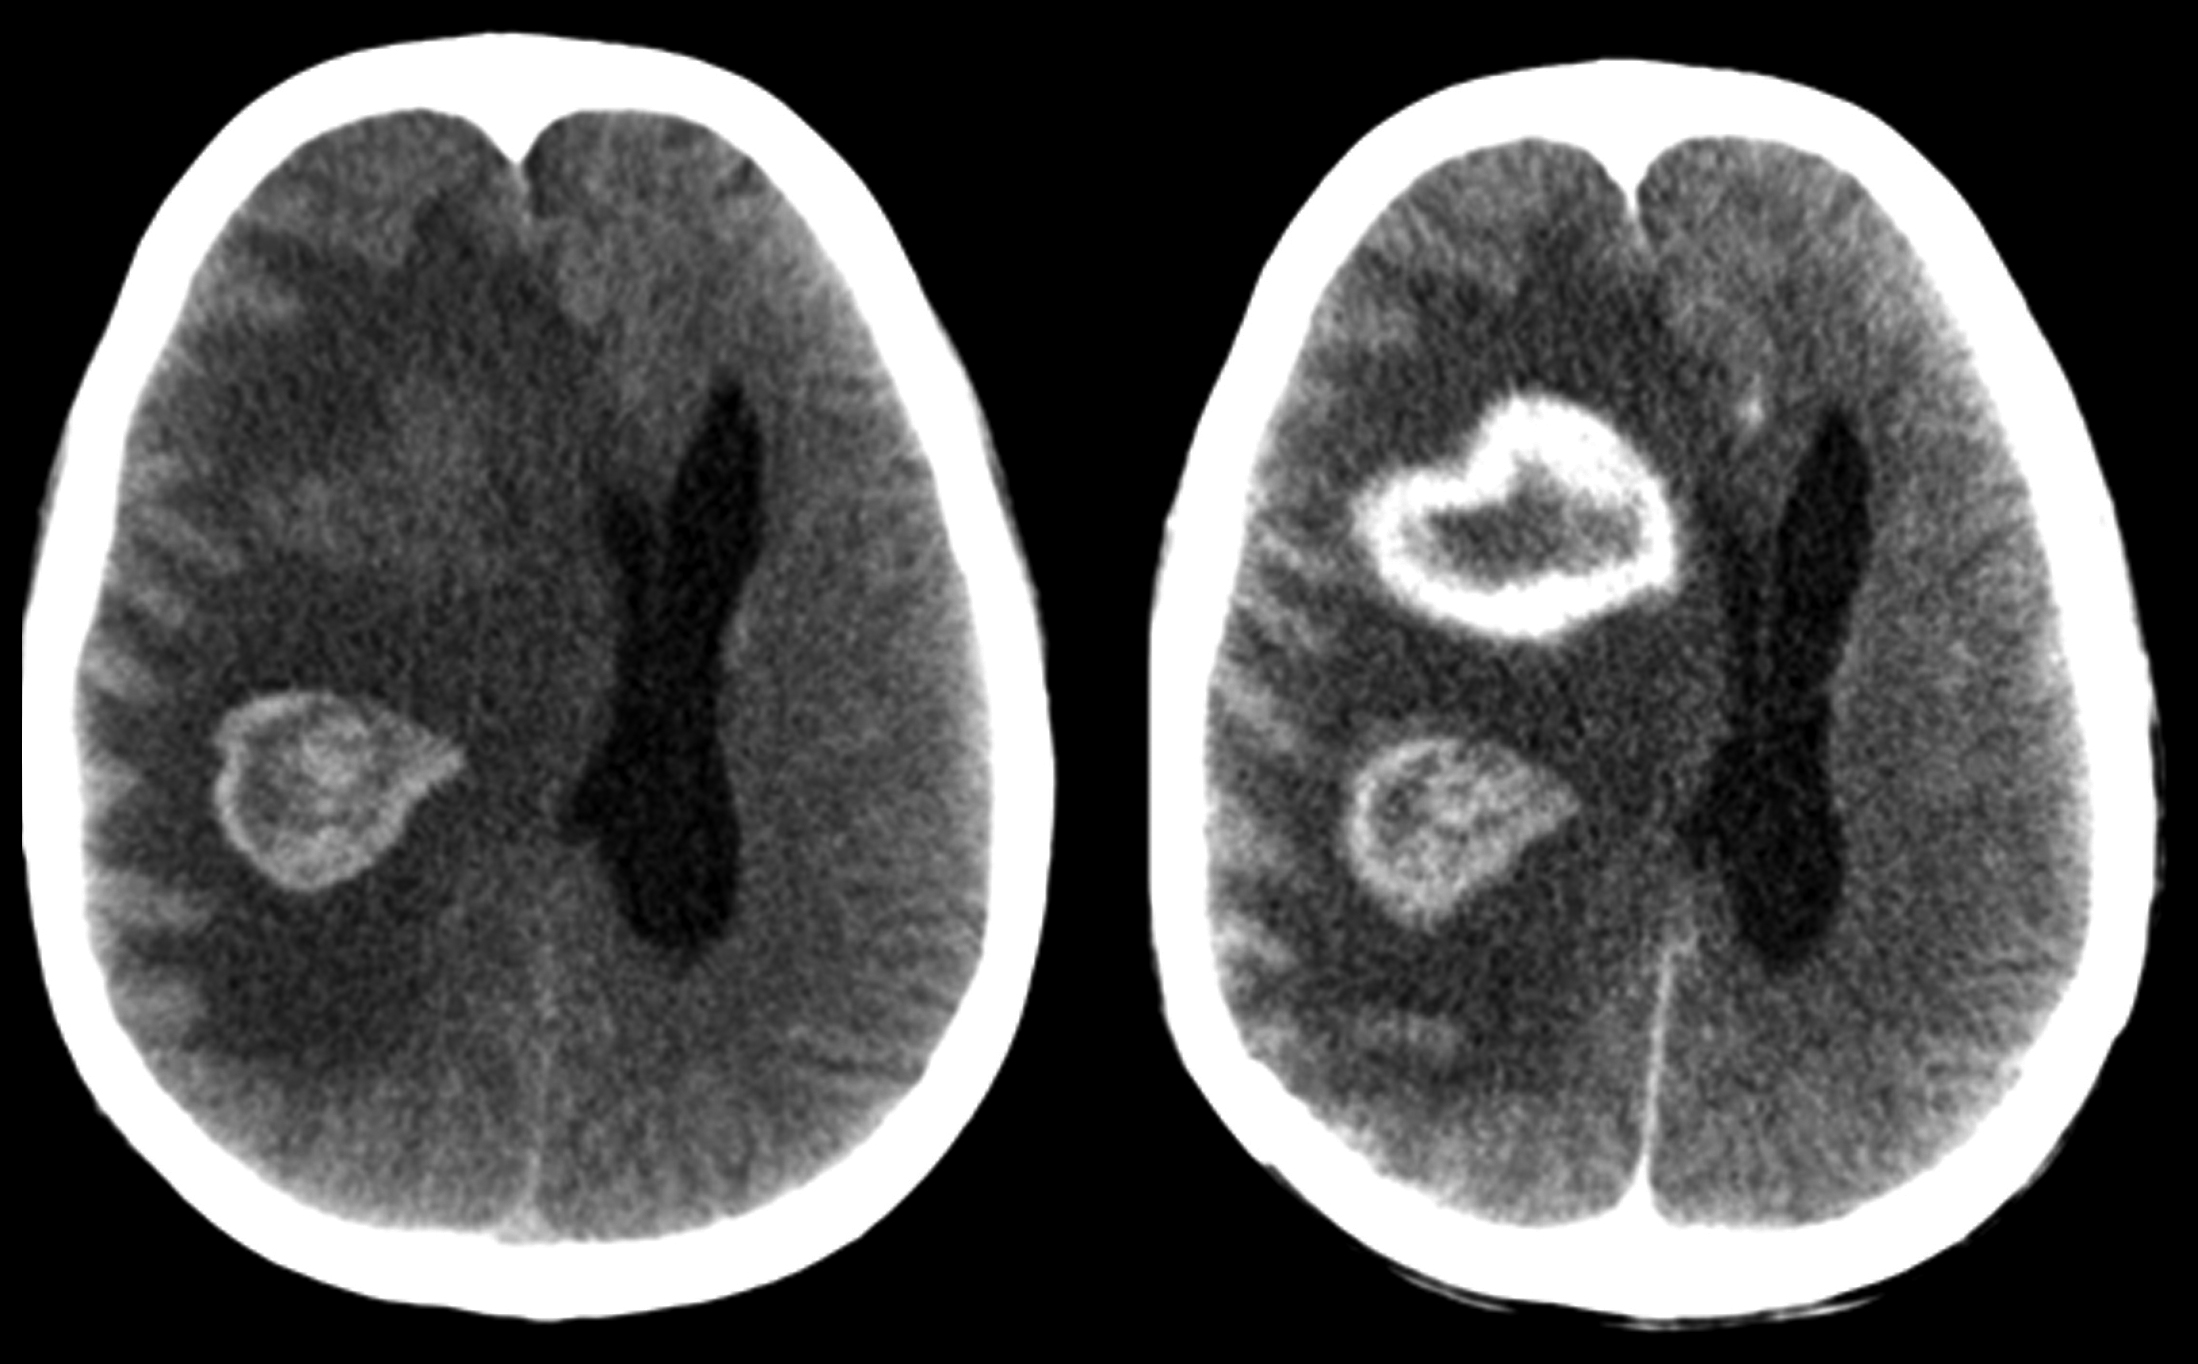

Se realiza TC de cráneo (Fig. 1), donde se constata la presencia de dos lesiones intra-axiales frontales derechas, con sectores espontáneamente hiperdensos en relación a sangrado. Ambas presentan realce en anillo grueso e irregular con el medio de contraste. En RM son de intensidad de señal heterogénea, hipointensas en T2/FLAIR (del inglés “fluid attenuated inversión recovery”), hiperintensas en T1, con realce periférico grueso, continuo e irregular con gadolinio. En secuencias eco de gradientes (GRE) se observan zonas de artificio de susceptibilidad magnética en relación a áreas de sangrado interno. En difusión-ADC (coeficiente de difusión aparente) se objetivan áreas periféricas de restricción y en el estudio de perfusión disminución del volumen sanguíneo cerebral (Fig. 2). Se completó estudio con TC de cuello, tórax, abdomen y pelvis, sin identificarse lesiones sugerentes de compromiso nodal, hepático o esplénico.

Con valores de CD4 de 37 cél/mm3 y carga viral de 283679 copias/ml, presenta peoría clínica, con depresión de conciencia, “score de coma de Glasgow” de 3, requiriendo intubación y asistencia respiratoria mecánica. En TC de control (Fig. 3), se constató aumento del tamaño lesional secundario a sangrado.

Figura 3

Control evolutivo

a) Corte sagital sin contraste.

b) Corte coronal con contraste iv. Frente a la peoría clínica se realizó tomografía de control. Se observa aumento de la lesión, secundario a sangrado intra-tumoral.